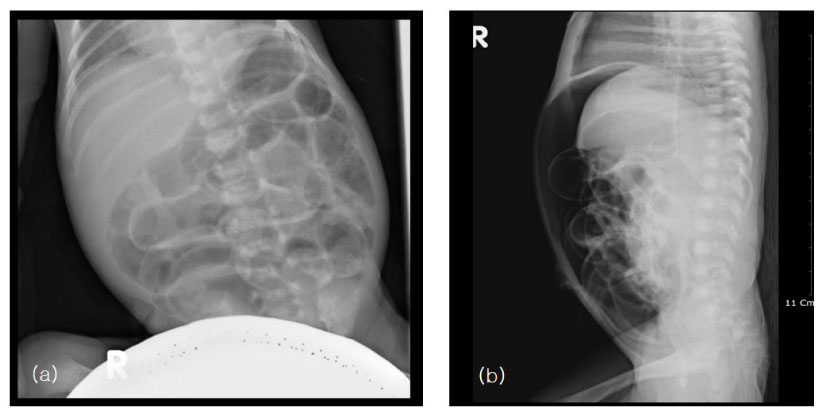

Masson's trichrome stain. Histopathologic examination of appendix shows a necrotic tissue and acute inflammatory cell in perforation site.

Fig. 3 Masson's trichrome stain. Histopathologic examination of appendix shows a necrotic tissue and acute inflammatory cell in perforation site.